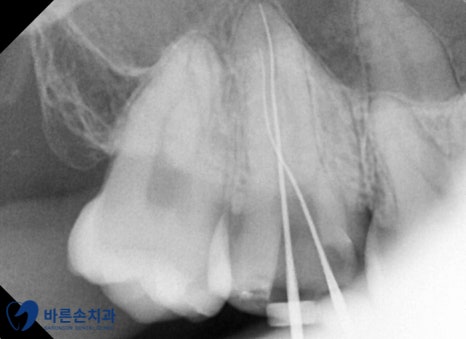

오른쪽 위 어금니의 신경치료를 먼저 시작하였습니다.

3번의 내원 끝에 신경치료를 마무리 합니다.

신경치료를 지르코니아 크라운 제작을 위한 본을 뜨고

일주일 뒤 오셔서 크라운을 붙여드렸습니다.